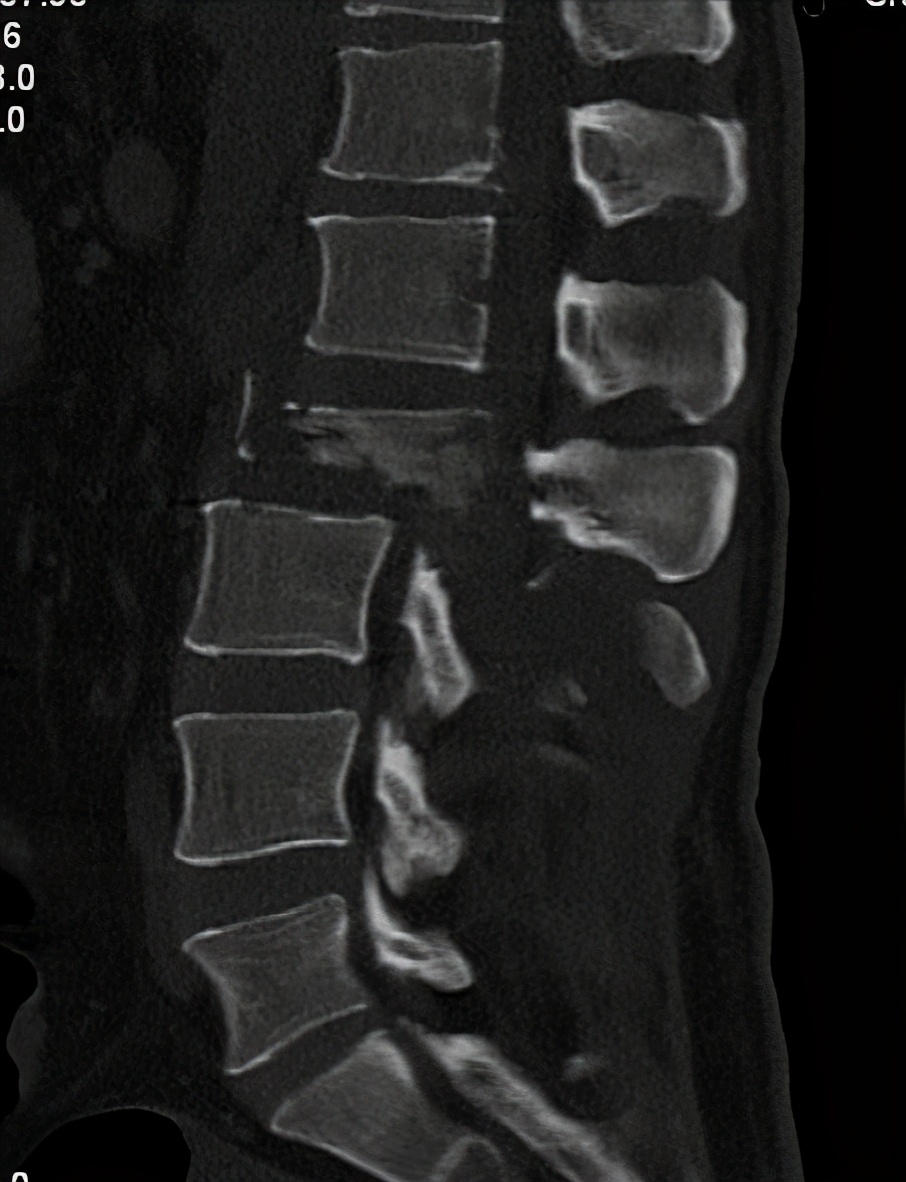

经过抢救后,检查身体见:患者 大小便功能障碍,双下肢完全瘫痪,感觉消失,肌力0级, 左下肢短缩外旋畸形,左大腿中下段肿胀明显。行X片和CT检查。

诊断为:1、 腰2椎体爆裂性骨折伴截瘫

腰椎CT

腰椎骨三维重建